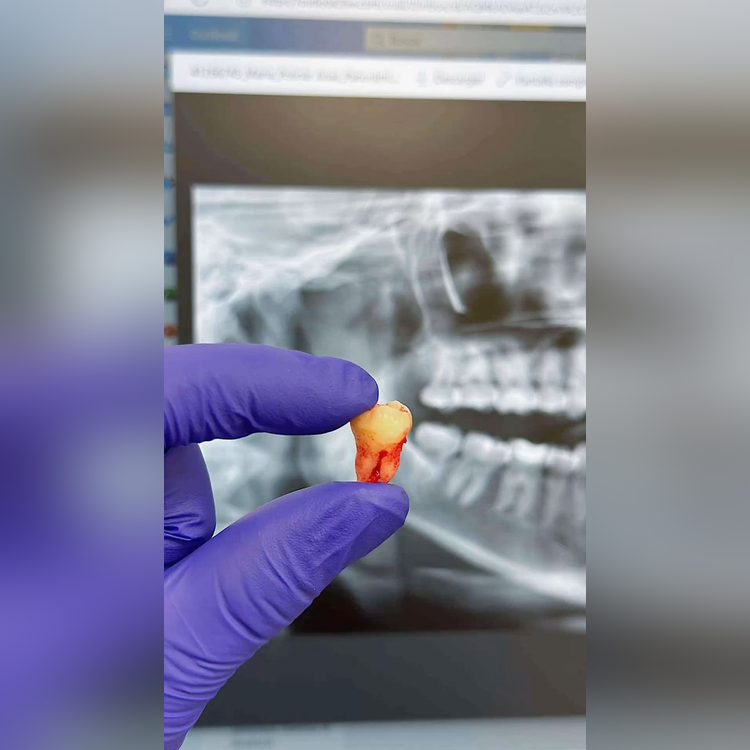

The extraction of an impacted wisdom tooth often necessitates a surgical procedure. This involves creating a small incision in the gums and safely removing the tooth. The procedure is performed under local anesthesia, sedation, or general anesthesia, depending on the patient’s comfort level and the complexity of the case.

- Surgical removal of tooth